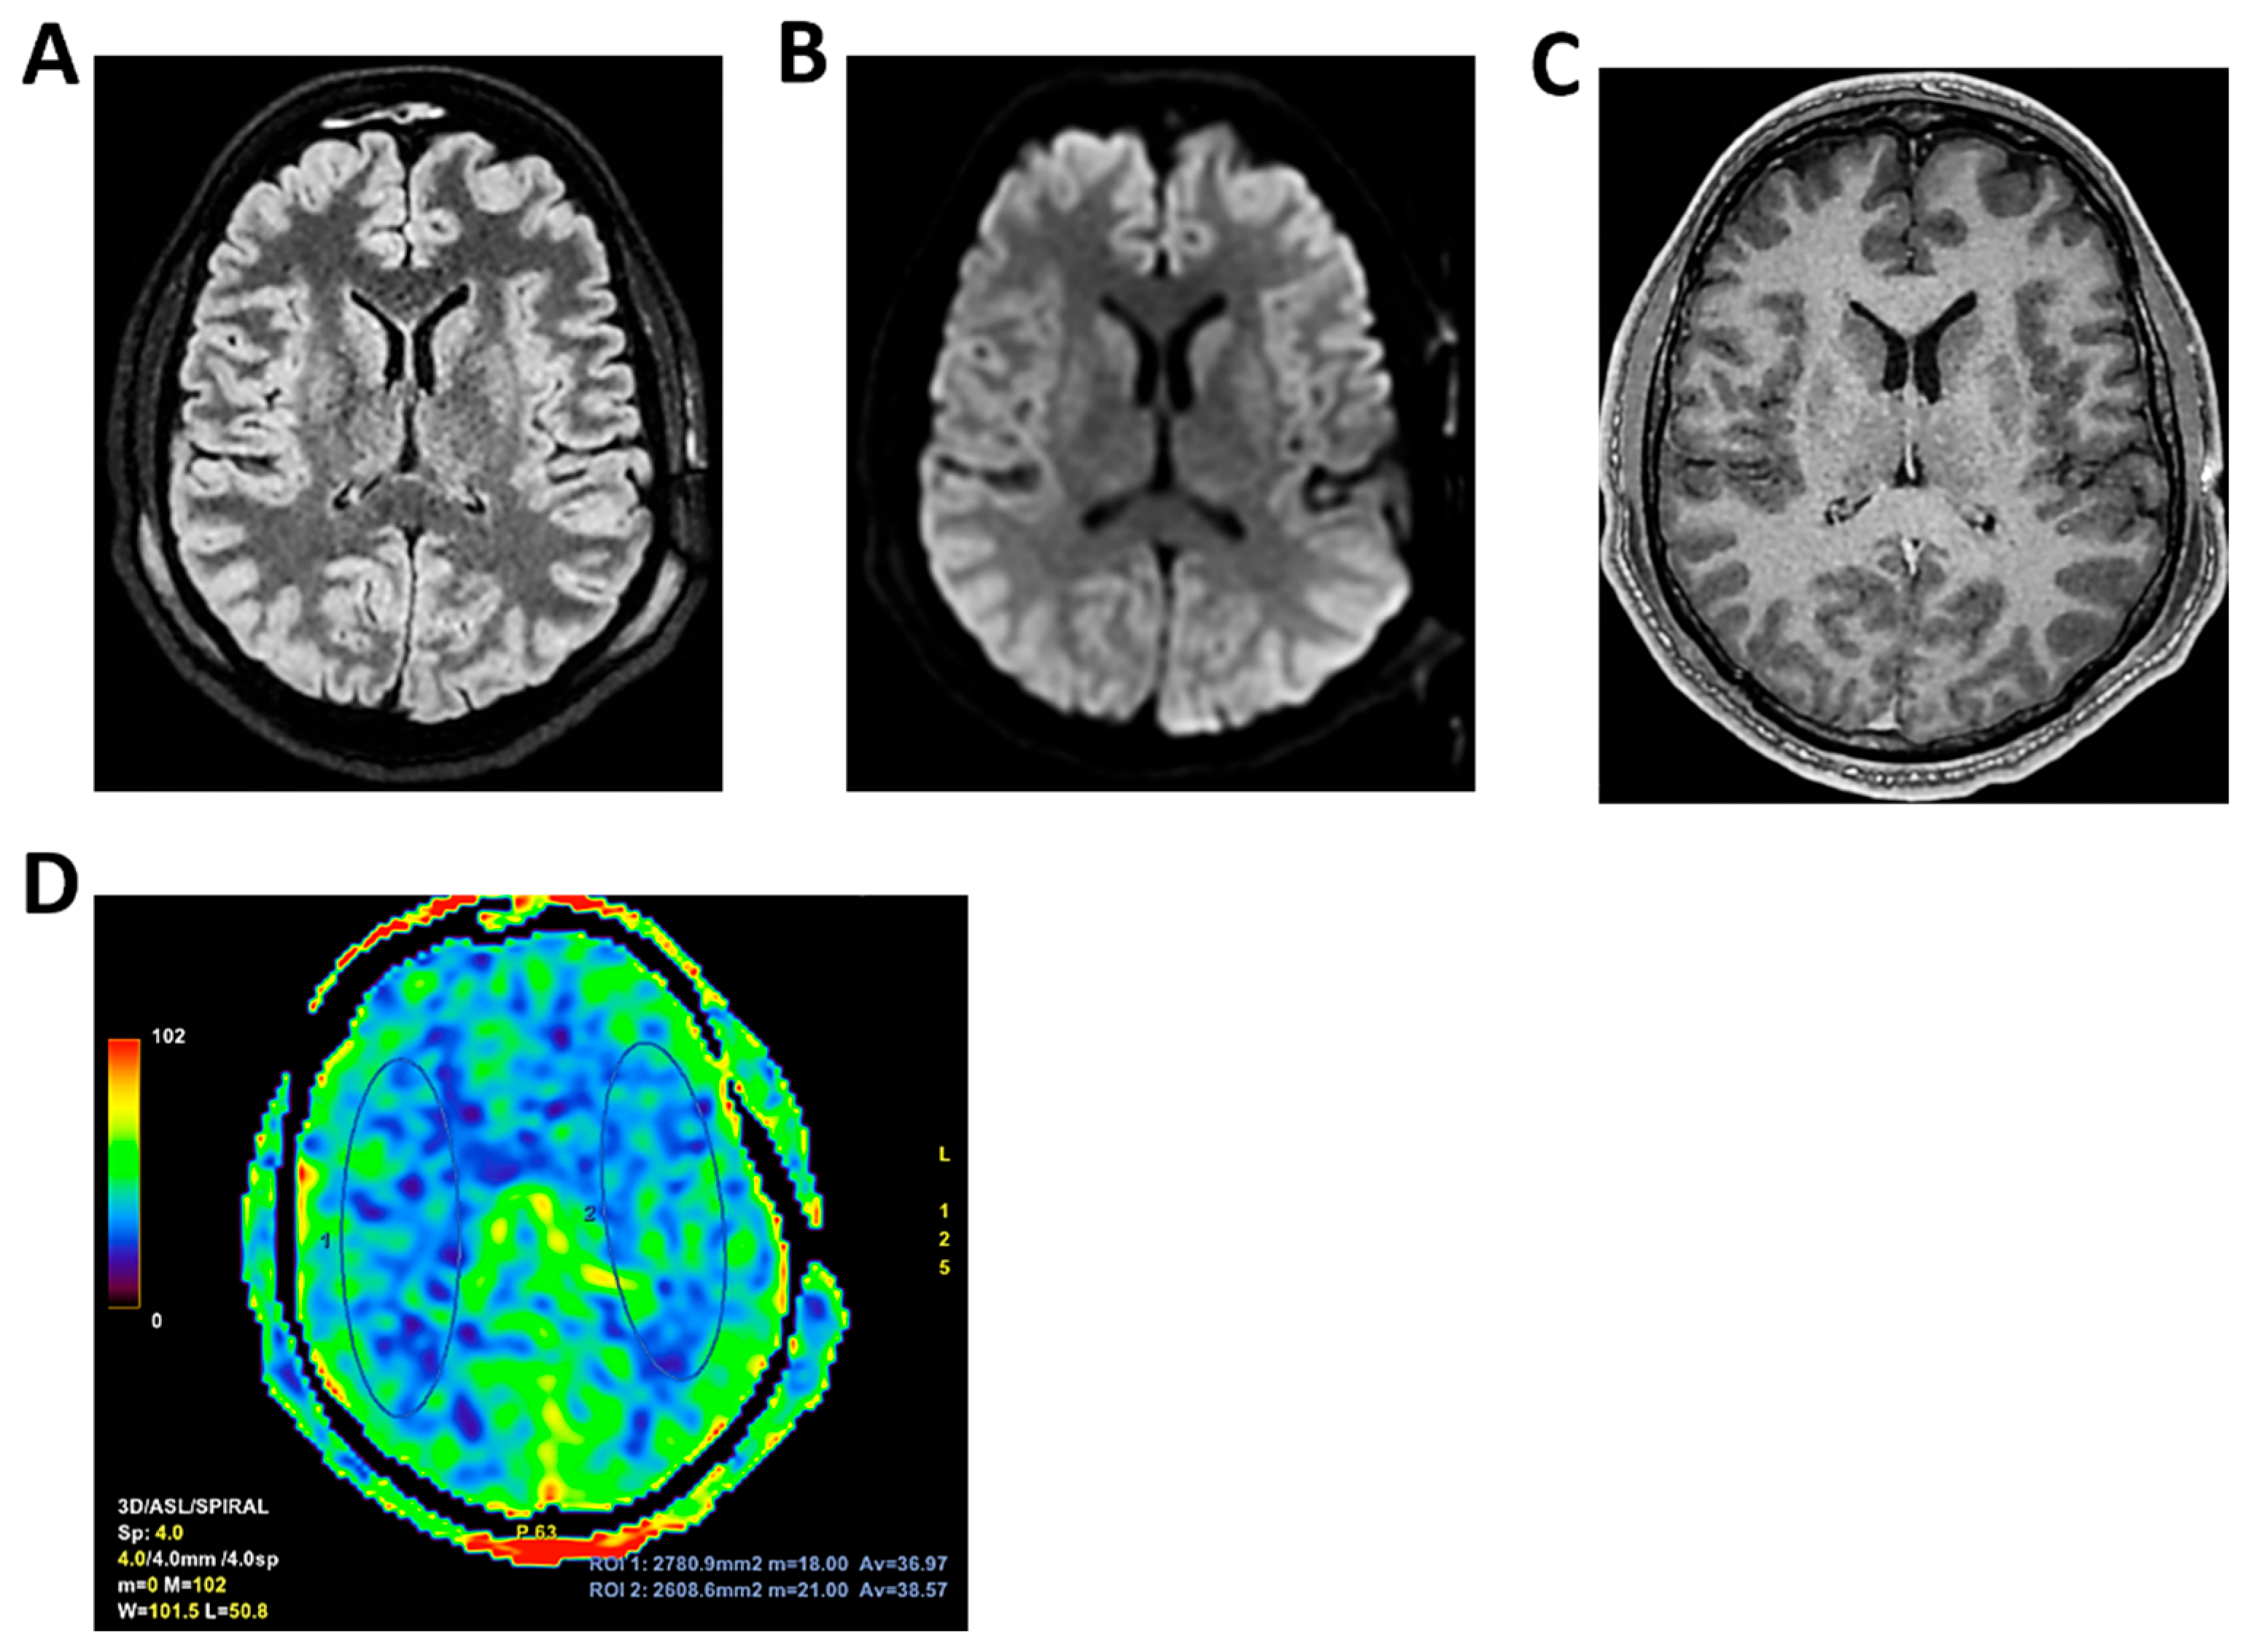

Figure 8.

MRI of patient 3 group 2. A 67-year-old woman with hypertension, depressive disorder, and hypothyroidism was brought to the ER in a confused state, following three days of abdominal pain, fever, neck pain, and headache. On arrival, she was drowsy but responsive to verbal stimuli and able to follow simple commands. Total-body CT showed no cranial or abdominal pathology except for a 6 cm rectal fecaloma; lungs were clear. A lumbar puncture revealed cloudy CSF with 1100 cells/mm3. FilmArray was positive for S. pneumoniae. She was treated with Rocephin and Tazocin and transferred to our ICU. On day 2, TCCD showed no flow abnormalities, with PI values of 1.2 (right) and 1.1 (left). (A) 3D axial FLAIR sequence shows multiple hyperintense areas, without significant diffusion restriction in axial DWI sequence, localized in bilateral corona radiata and centrum semiovale and leveled material of likely inflammatory nature in both occipital horns of the lateral ventricles. (B) The perfusion study revealed normal and symmetrical CBF values. Blue and yellow circles indicate the ROI used for quantitative CBF analysis.